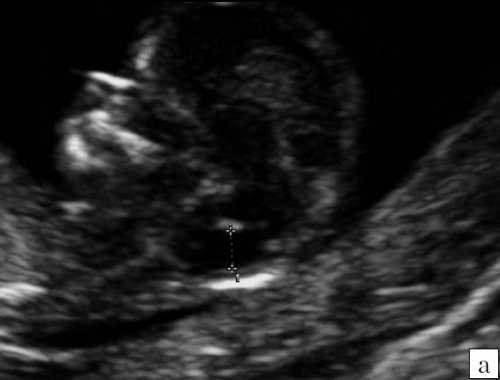

Особенностями визуализации этих структур является их гипо/анэхогенность. Так, при сроках 11-14 недель беременности таламус, ствол мозга, средний мозг выглядят практически анэхогенными. Итак, нормальная ультразвуковая анатомия этих структур головного мозга плода имеет следующие особенности: ствол и IV желудочек выглядят как анэхогенные продолговатые структуры, имеющие непосредственную близость (как бы выходящие) из диэнцефалона и среднего мозга. Все выше перечисленные анатомические структуры могут быть измерены и должно быть оценено их взаиморасположение (рис. 2, а).

а) На эхограмме:

1 - ствол мозга;

2 - интракраниальное пространство, или IV желудочек;

3 - большая цистерна головного мозга;

4 - воротниковое пространство.